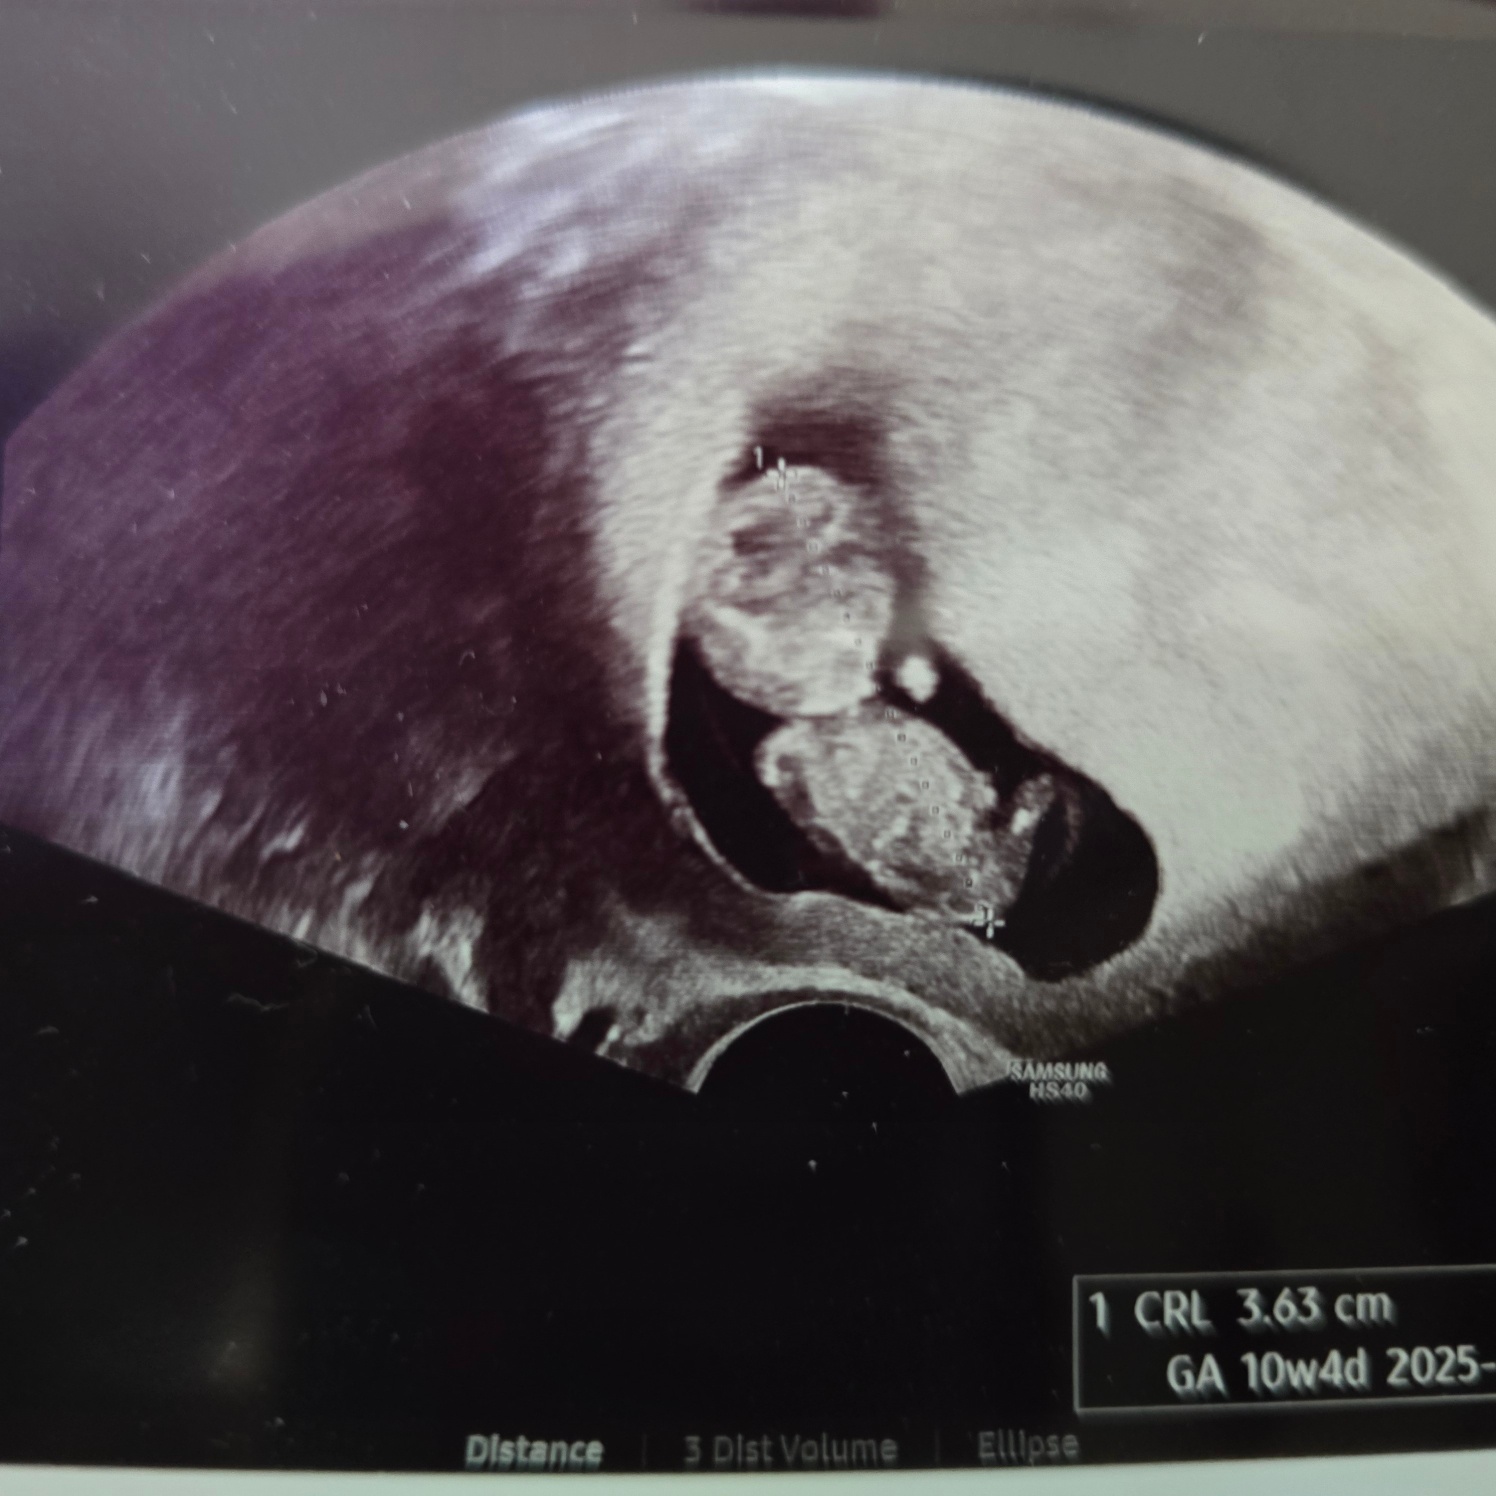

10주 6일 차 - 조금씩 따라잡는 뚝딱이!

지난주까진 4일씩 느렸는데 10주 6일 차엔 이틀 느린 10주 4일 차 크기!!

오구 장하다 장해 열심히 크고 있구나!!ㅎㅎㅎ

일주일마다 새로운 모습으로 쑥쑥 크는 뚝딱이가 기특하기만 하다.ㅎㅎ

난임병원에서의 마지막 초음파! 다음부턴 출산병원으로 다닌다.ㅎㅎ